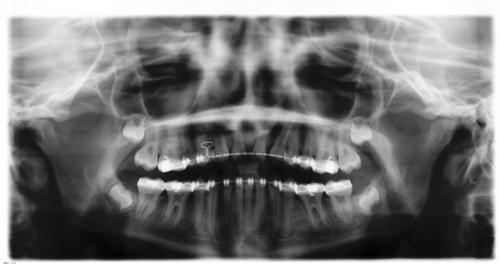

Röntgenbefund

Vor und nach der Behandlung

Die roten Punkte auf der linken Röntgenaufnahme markieren die Milchbackenzähne ohne Nachfolger, die ausgleichend enfernt wurden. Auf der rechten Aufnahme sieht man die Situation nach dem Lückenschluß.